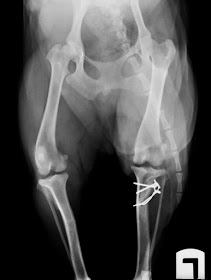

Se ha

cortado la cresta tibial y puesto que la luxación es lateral se ha desplazado

medialmente y fijado en su nueva posición con dos agujas de Kirschner y un

cerclaje.

*Las

flechas rojas señalan la posición inicial de la cresta tibial y el

desplazamiento hacia la nueva posición logrado con la transposición de la

misma.

Siento que

las imágenes no estén todo lo bien posicionas que debieran, pero especialmente

en la última se aprecia muy bien el corte en la cresta tibial y su sujeción con

agujas y cerclaje.